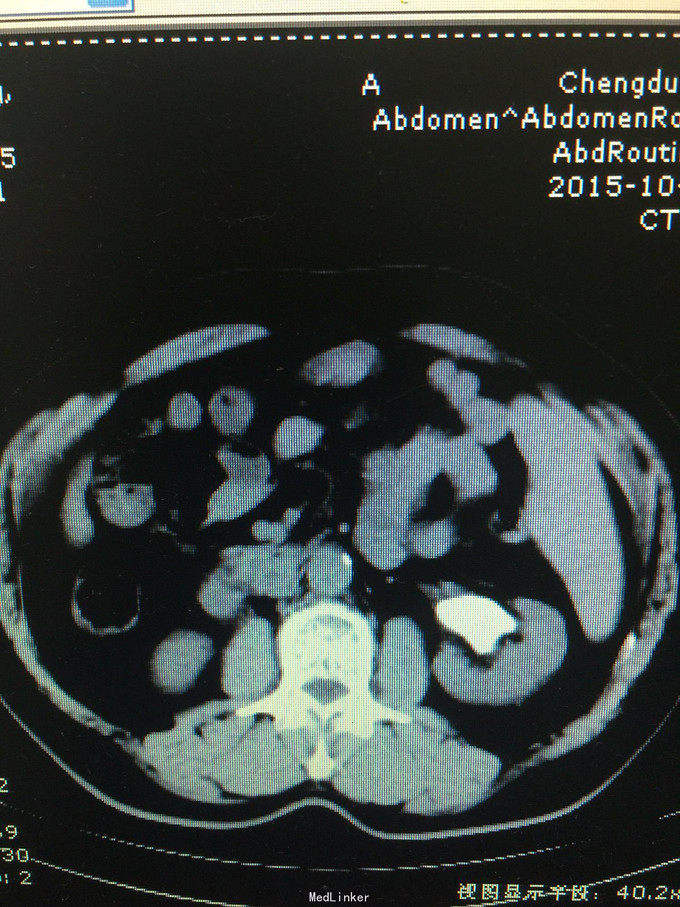

患者男,59岁,因检查发现左肾巨大铸型结石3天入院 病史:患者检查发现左肾结石,无发热,无血尿,无腰痛,食欲,睡眠均正常。

诊断考虑左肾铸型结石。 处理:经皮肾球囊扩张,钬激光加气压弹导碎石,手术顺利,术中术后出血少,术后复查未见结石残留。患者痊愈出院。

随着输尿管软镜手术的不断成熟,经皮肾碎石术量不断减少,但对于巨大铸型结石,经皮肾清石率明显高于输尿管软镜,尤其对于大通道手术,我科随访并未见明显出血增加,住院时间增加等。